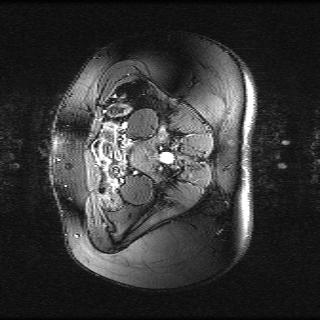

Test data: For evaluation, we used the ten 352352 MRI images in Fig. 2, which were not in the training dataset. The measurements were constructed using (1) with complex AWGN whose variance was adjusted to give a pre-masking SNR of 40 dB. For the multicoil experiments, we used coil sensitivities simulated using the Biot-Savart law, while in the single-coil case, we used .